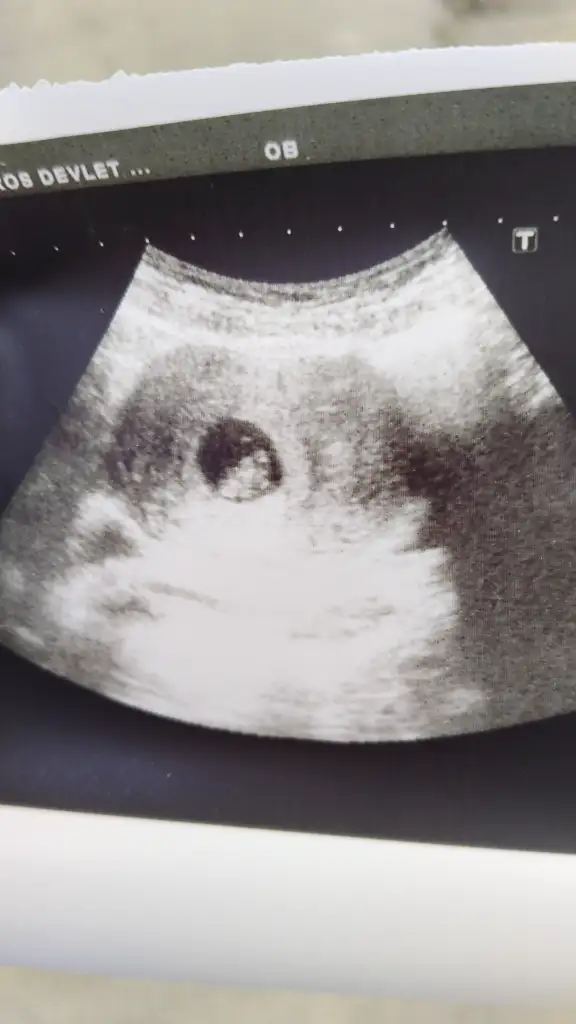

Çok tşk ederim güzel dileklerin için kalp atisimizi 7 haftada duyduk 10 haftalık olduk sana slm vermeye geldik bebisimle

Size çok tşk ederim herşey yoluna girdi değerlerim normal seviyede yükseldi ve dün keseyi gördük 5+2 şu an çok şükür